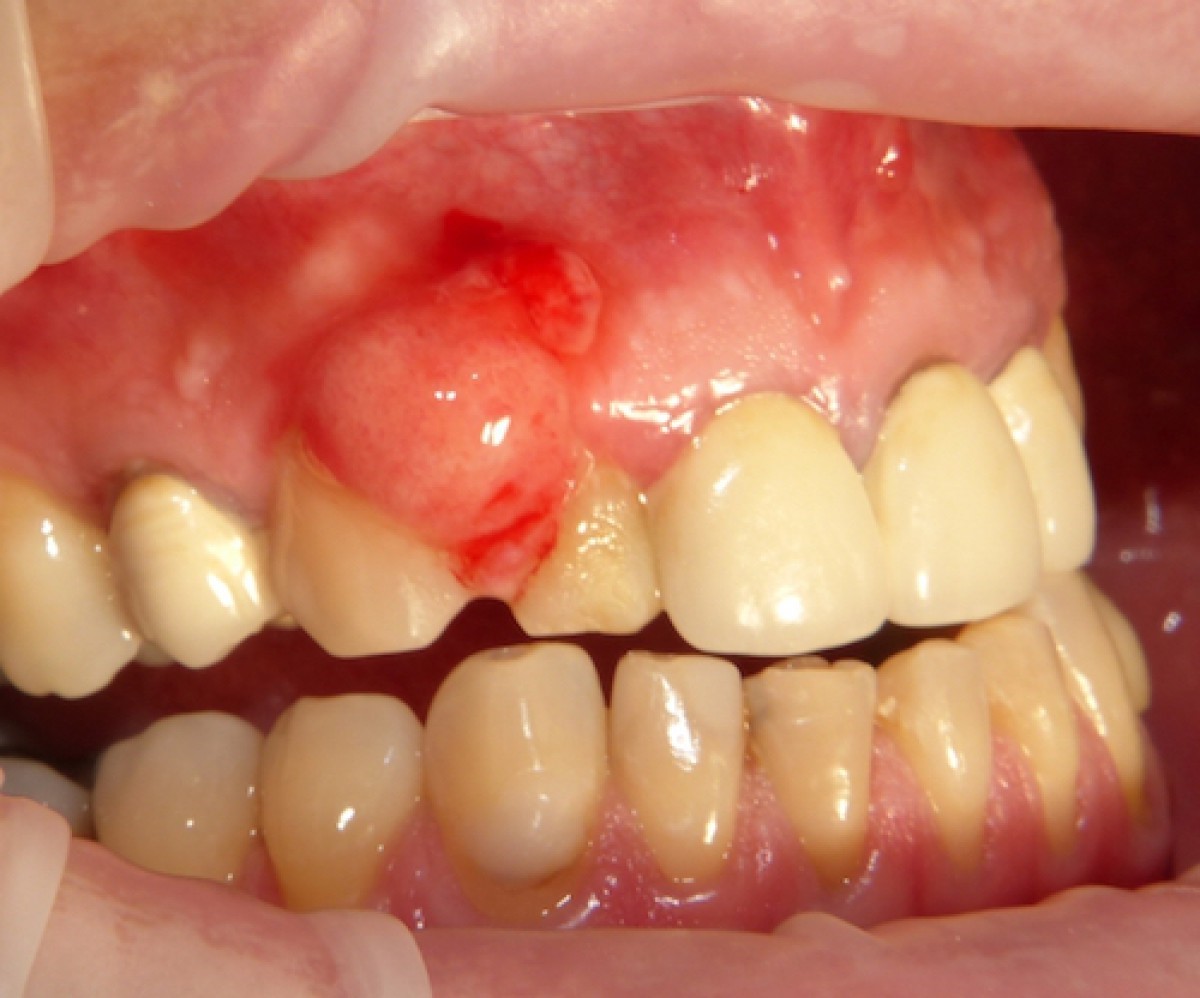

Viêm chân răng hàm có mủ

Hình ảnh áp xe mủ ở chân răng